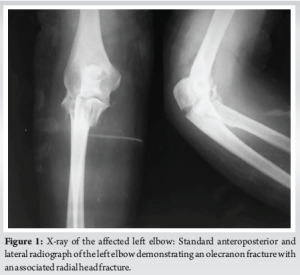

Standard AP and lateral radiographs of the left elbow (Fig. 1) revealed an olecranon fracture with a radial head fracture, which still did not explain the gross instability in both planes. Hence, a CT scan (Fig. 2) was done, which revealed a fracture of the coronoid (Regan and Morrey Type II, O’Driscoll Type II) along with elbow subluxation [6,7]. Ideally, an MRI should have been done to see the status of the ligaments, but we were unable to get one due to some logistic concerns at our institute. As the injury was already 3 weeks old and did not want to delay further, we decided to go ahead with the surgery, and had any ligamentous instability been found after bony fixations during the surgery, we would have repaired that by suture anchors. All of this was explained to the patient and then only he was posted for surgery.